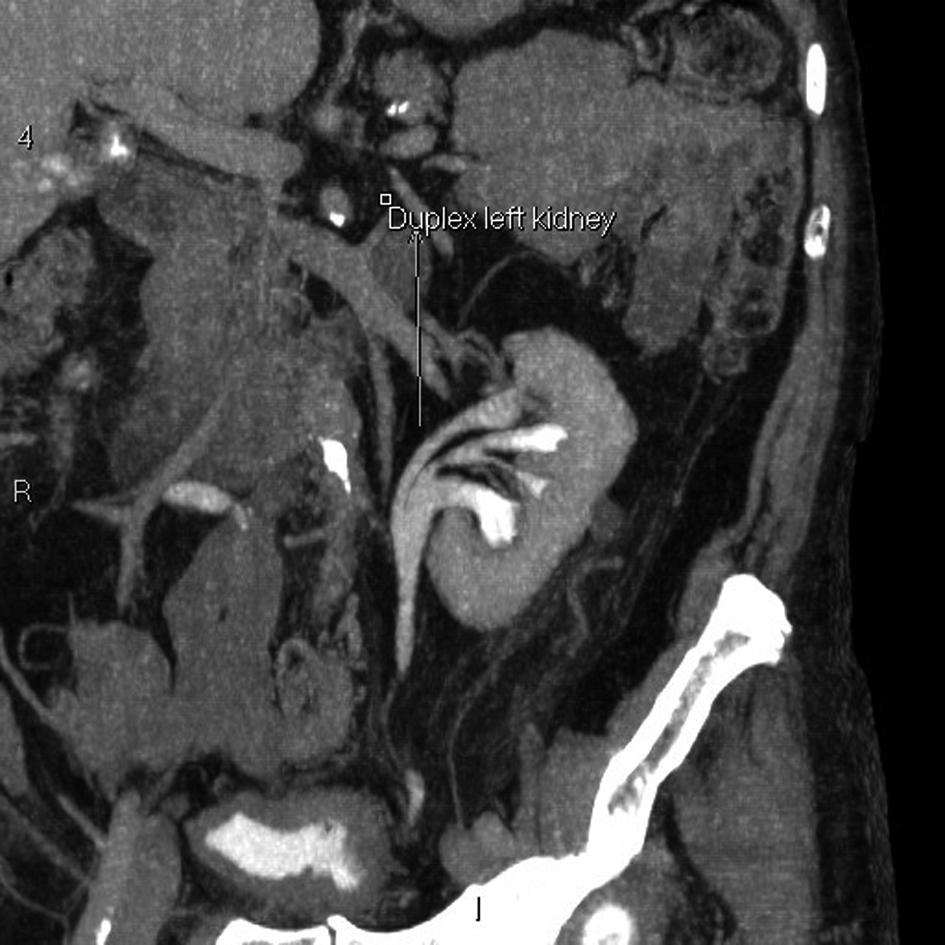

An 83-year old male with benign prostatic enlargement (BPE) presented with acute urinary retention with renal failure, constipation and weight loss. On examination, he had large bilateral asymptomatic inguinal herniae. Following catheterisation and medical renal failure management, a contrast-enhanced CT scan was performed to investigate his constitutional symptoms. An incidental finding was partial left ureteral duplication, and urography revealed that the distal part of one limb looped into the left inguinal hernia before inserting into the bladder (Fig. 1-4). The patient’s renal function normalised with catheterisation, which was definitive management of his BPE due to medical co-morbidities.

![]() Click for large image | Figure 1. Coronal reconstruction of abdominal and pelvic CT urogram demonstrating duplex left kidney. |